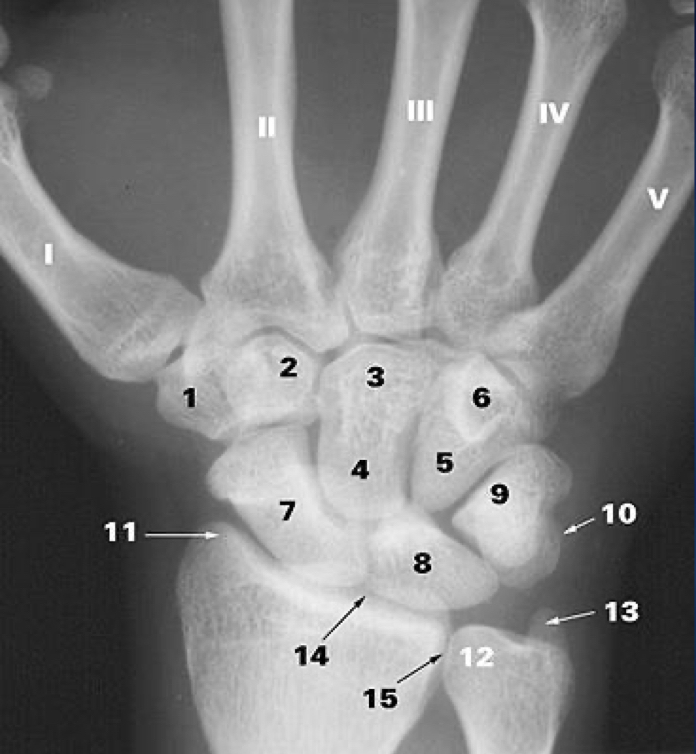

1

What is 1?

trapezium b.

2

What is 2?

trapezoid b.

3

What is 3?

capitate b.

4

What is 5?

5

6

What is 7?

scaphoid b.

7

What is 8?

lunate b.

8

What is 9?

triquetrum b.

9

What is 10?

pisiform

10

What is 11?

styloid process of the radius

11

What is 12?

head of the ulna

12

What is 13?

styloid process of ulna